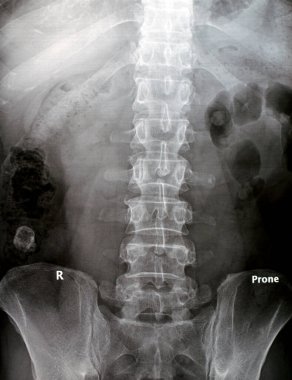

Sırt ve kereste omurgasının röntgen ışınları spondilotik değişimleri, sırt ve kereste dikenlerinin düzleştirilmesini, omurgalar arası disk alanlarının bozulmamış olduğunu, sırt ve kereste dikenlerinin Spondylosis 'inin bozulmamış olduğunu gösterir.